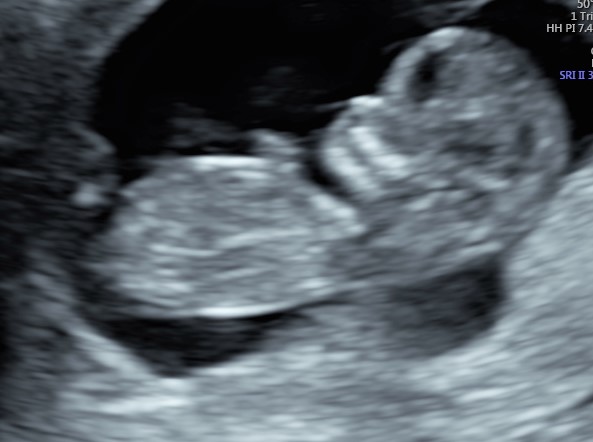

Indipendentemente dalla nostra scelta, è di capitale importanza fare comunque una ecografia fra la 11° e la 13° settimana. Infatti già a questa epoca gestazionale siamo in grado di condurre un’iniziale valutazione morfologica. Ma soprattutto questo è la finestra di opportunità per studiare la translucenza nucale. In realtà questa ampia finestra di tre settimane ha il suo momento più favorevole a 11 settimane e mezza e inizio dodicesima.

Si va a misurare quindi attraverso una ecografia lo spazio dietro la nuca: è una fisiologica raccolta di linfa che tende ad aumentare in diverse situazioni patologiche risultando essere un indice generale di buon andamento della gravidanza dove più è sottile più siamo tranquilli a riguardo di patologie cromosomiche, malformazioni cardiache, ed alcune malattie genetiche.

In questi 4/5 centimetri la risoluzione degli apparecchi moderni riesce a fare una prima valutazione morfologica, per vedere che ci siano tutti i “necessori” ed eventualmente anche accessori: cercando è possibile evidenziare il tubercolo genitale (sempre che il piccolo decida di essere collaborante e mostrare le proprie grazie). Si chiama così perché clitoride e pisellino hanno le stesse dimensioni a questa epoca, ma è possibile riconoscerli in base all’angolo rispetto al corpo: parallelo al corpo per le signorine, verso l’alto per i maschietti. Attenzione però la sensibilità, ovvero quanto ci azzecchiamo, è intorno al 60%.

La parte morfologica è molto importante, riusciamo a studiare l’estremo cefalico – a questa epoca il cervello fetale è molto semplice – , il massiccio facciale con occhi, naso bocca, le orecchie sono abbastanza facili da essere evidenziate. Nel torace oltre ai campi polmonari possiamo vedere il cuore battere ritmicamente e confermare la presenza delle quattro camere cardiache. Nell’addome riusciamo ad evidenziare lo stomaco e l’inserzione del cordone ombelicale. Si nota la presenza della vescica e del tubercolo genitale. Si possono esplorare tutti e quattro gli arti.

Per i genitori vedere sotto i propri occhi prendere forma il tesorino risulta una esperienza indimenticabile e impareggiabile al limite fra incredulità e la sorpresa come tutto sia già presente seppur in scala ridotta.